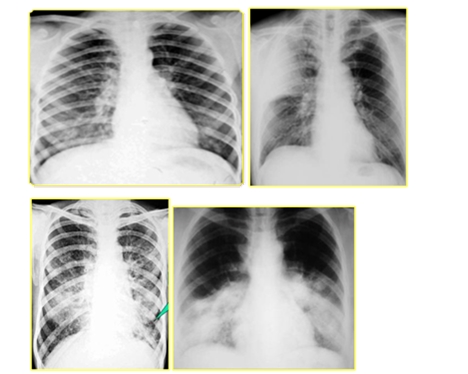

二、肺部感染

肺部感染=咳嗽、咳痰(間質(zhì)性肺炎無痰)+發(fā)熱+白細胞增高,中性粒細胞比例增高

| 肺部感染類型 | 特點 |

| 小葉性肺炎(支氣管肺炎) | 兩肺中下野散在斑片影 |

| 大葉性肺炎 | 大片致密影 |

| 間質(zhì)性肺 | 網(wǎng)狀或小結(jié)節(jié)狀影 |

| 傳染性非典型肺炎 | 不同程度的片狀、斑片狀浸潤性陰影或呈網(wǎng)狀改變,進展迅速者呈大片狀陰影 |